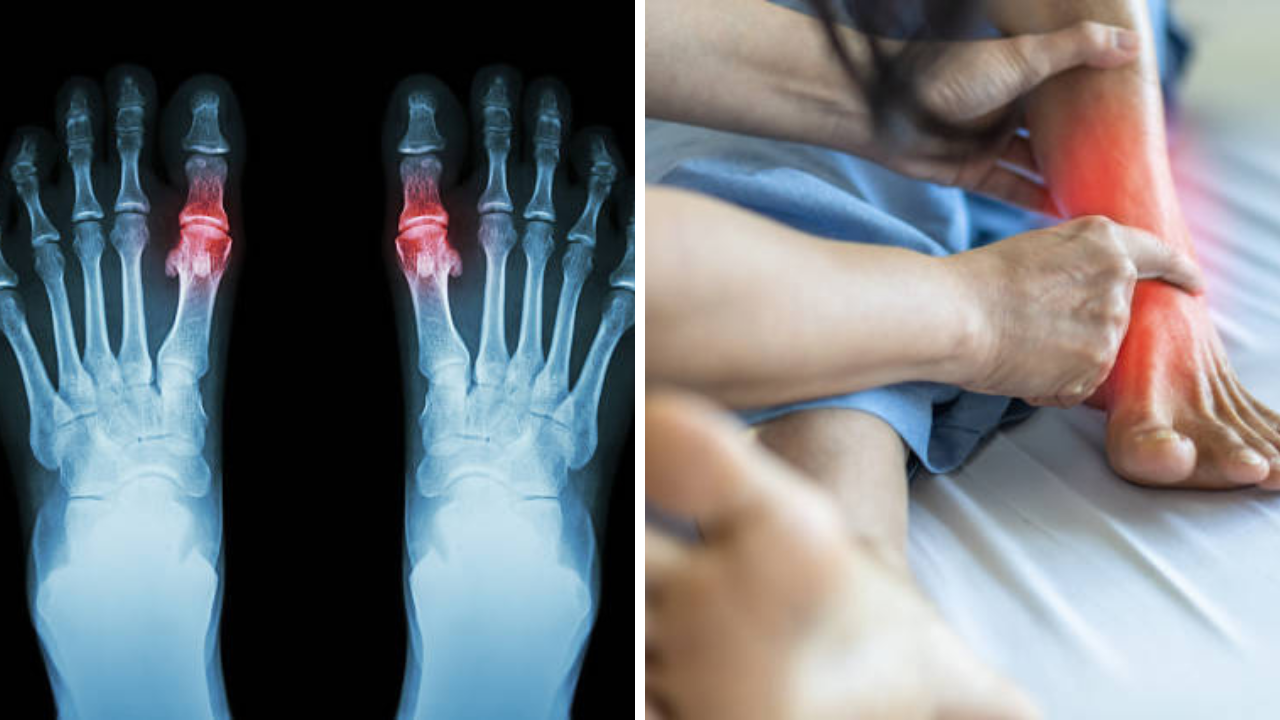

Uric Acid च्या रुग्णांनी टाळा 3 भाज्यांचे सेवन, संधिवाताने व्हाल हैराण